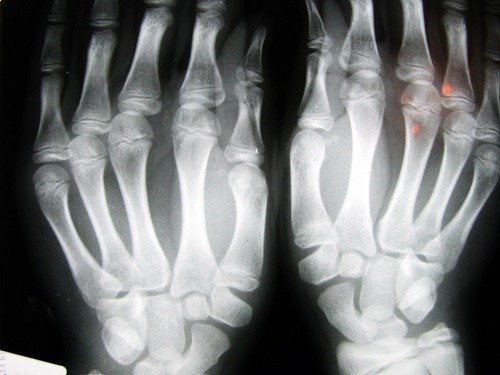

Osteoporose is een botziekte die een afname van de botdichtheid veroorzaakt. Deze ziekte wordt gekenmerkt door botten die makkelijker breken. Dat komt omdat in plaats van bot, er allemaal kleine holtes gaan ontstaan.

Deze ziekte wordt ook wel een stille aandoening genoemd, omdat het vaak onopgemerkt blijft totdat er schade aan de botten is ontstaan.

Breuken komen vaak voor in de polsen en ook in de heupgewrichten. Die laatste vorm is de ernstigste soort botbreuk, omdat er dan onmiddellijk chirurgische ingrepen nodig zijn en het fractuur ernstige gevolgen voor de gezondheid van de patiënt kan hebben.